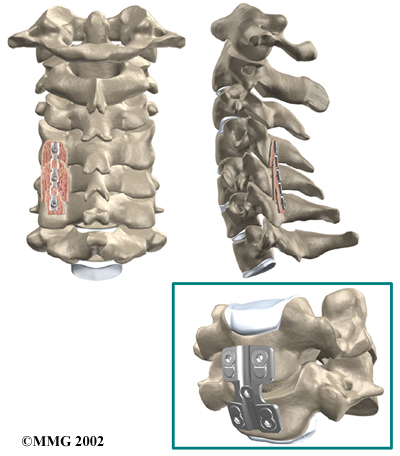

Cervical Fusion

A fusion surgery joins two or more bones into one solid bone. The purpose for doing spinal fusion is to increase the space between the vertebrae and to keep the sore joint from moving. This is usually done by placing a small block of bone graft in the space where a disc was removed. Opening up more space enlarges the neural foramen, takes pressure off the nerve roots, and eases tension on the facet joints. Cervical fusion is used to treat neck problems such as cervical radiculopathy, disc herniations, fractures, and spinal instability. There are two main types of fusion for neck problems.

- Anterior Discectomy and Fusion: Anterior discectomy and fusion is done through the front of the neck. After taking out the disc (discectomy), the disc space is filled with a small graft of bone. The bone is allowed to heal, fusing the two vertebrae into one solid bone.

Small Graft of Bone

The bone graft needs time to heal in order for the fusion to succeed. This requires the neck to be held still. After cervical fusion surgery, patients usually have to wear a special neck brace for several months. These neck braces are often bulky and restrictive. Recently, surgeons have begun using metal plates and screws (often referred to as instrumentation) to lock the bones in place. The instrumentation is fastened to the vertebrae, where it holds the bones still while the graft heals.

Locking the Bones in Place